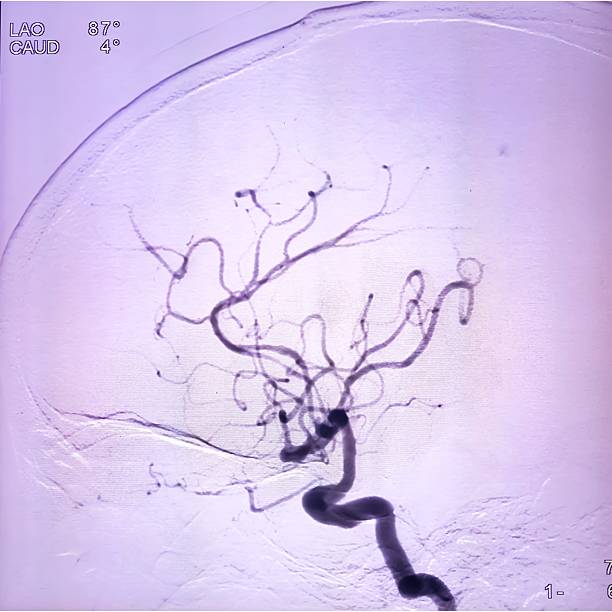

뇌경색은 뇌혈관이 막히면서 해당 부위에 혈액이 공급되지 않아 뇌세포가 손상되는 질환이에요.

**‘허혈성 뇌졸중’**이라고도 하며, 전체 뇌졸중의 약 **70~80%**를 차지할 만큼 흔한 형태입니다.

보통은 고혈압, 당뇨, 고지혈증, 흡연, 심장질환 등이 주요 원인으로 작용하죠.